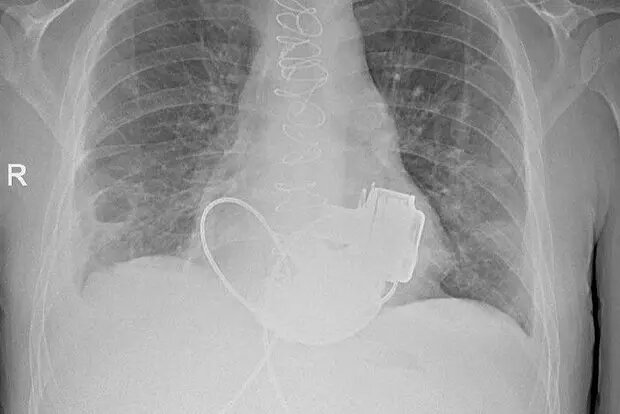

В Санкт-Петербурге, в стенах Мариинской больницы, произошёл настоящий прорыв в отечественной медицине — 36-летний пациент с тяжёлой формой сердечной недостаточности впервые в стране получил имплантацию сразу двух искусственных желудочков сердца. Этот случай уже называют уникальным, ведь подобная операция стала первой в России и продемонстрировала высочайший уровень профессионализма медицинской команды под руководством главного врача Игоря Реутского вместе с ведущим академиком в области сердечно-сосудистой хирургии Геннадием Хубулавой.

Команда Мариинской больницы под руководством Игоря Реутского, проявив высочайшую компетентность и решительность, приняла инновационное решение: вместо установки одного искусственного желудочка, как делалось ранее, было решено имплантировать одновременно оба. Это непростое вмешательство длилось около четырёх часов, и основной сложностью стала необходимость идеальной синхронизации работы двух искусственных механизмов.

Геннадий Хубулава, возглавивший бригаду самых опытных хирургов, отметил, что несмотря на все сложности, врачам удалось достичь синхронной работы обоих искусственных желудочков благодаря новейшим медицинским технологиям и уникальному опыту петербургских специалистов. Это не просто шаг вперёд для кардиохирургии, но и весомое подтверждение высокого статуса Мариинской больницы как одного из ведущих профильных центров страны.